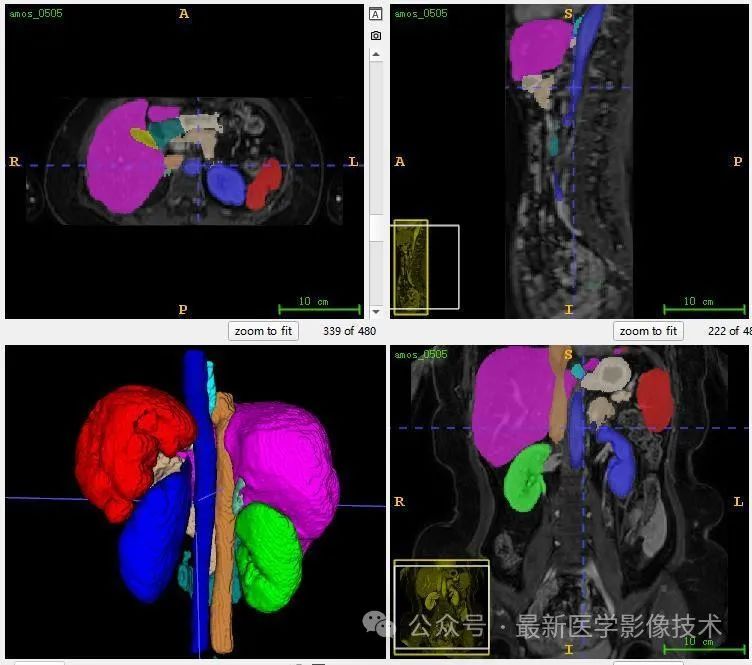

12、验证集分割结果

左图是金标准结果,右图是预测结果。

13、测试集分割结果